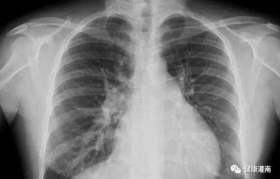

胸片检查是常见的医学影像学检查项目,其费用因地区、医院级别、检查方式等因素而异。本文将全面解析胸片的...